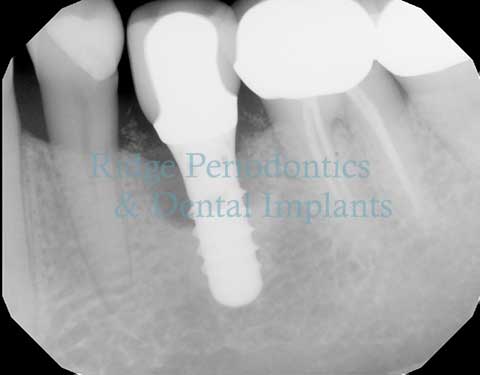

Laser Periodontal Regeneration

Advanced laser therapy for treating peri-implant disease and maintaining the health of dental implants.